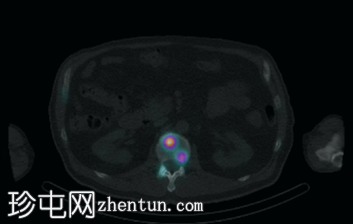

轴位融合

SPECT/CT

脊柱、肋骨、骨盆、颅骨、肩胛骨、胸骨、左侧肱骨和双侧股骨干可见多处放射性示踪剂摄取异常增高,与SPECT-CT扫描图像上显示的硬化病灶相对应。双肾未见放射性示踪剂活性。

骨骼内多处局灶性放射性示踪剂摄取增高,符合骨转移;肾脏内无放射性示踪剂活性,与超扫描结果一致。